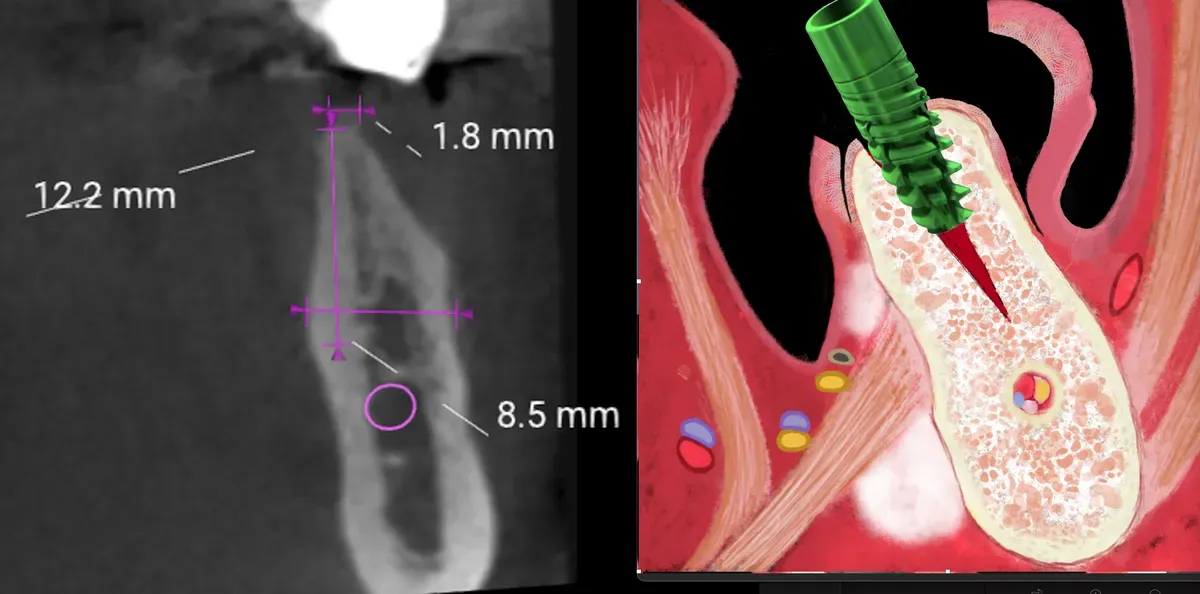

La sopravvivenza implantare raggiunge il 98.1% con intervallo di confidenza al 95% tra 96.9% e 98.9%. Il guadagno osseo medio ottenuto con le tecniche di espansione crestale si attesta a 3.3mm, con un range che va da 1.6mm a 5.3mm a seconda dei casi. Le complicanze risultano gestibili quando si applica la tecnica appropriata.

I limiti esistono ma sono diminuiti:

L’osso A1 mandibolare è difficile ma fattibile con spugnosa centrale. La rigenerazione verticale funziona bene per casi lievi come la classificazione V1 secondo BDIZ EDI. Le creste a clessidra no, la cresta deve allargarsi progressivamente.